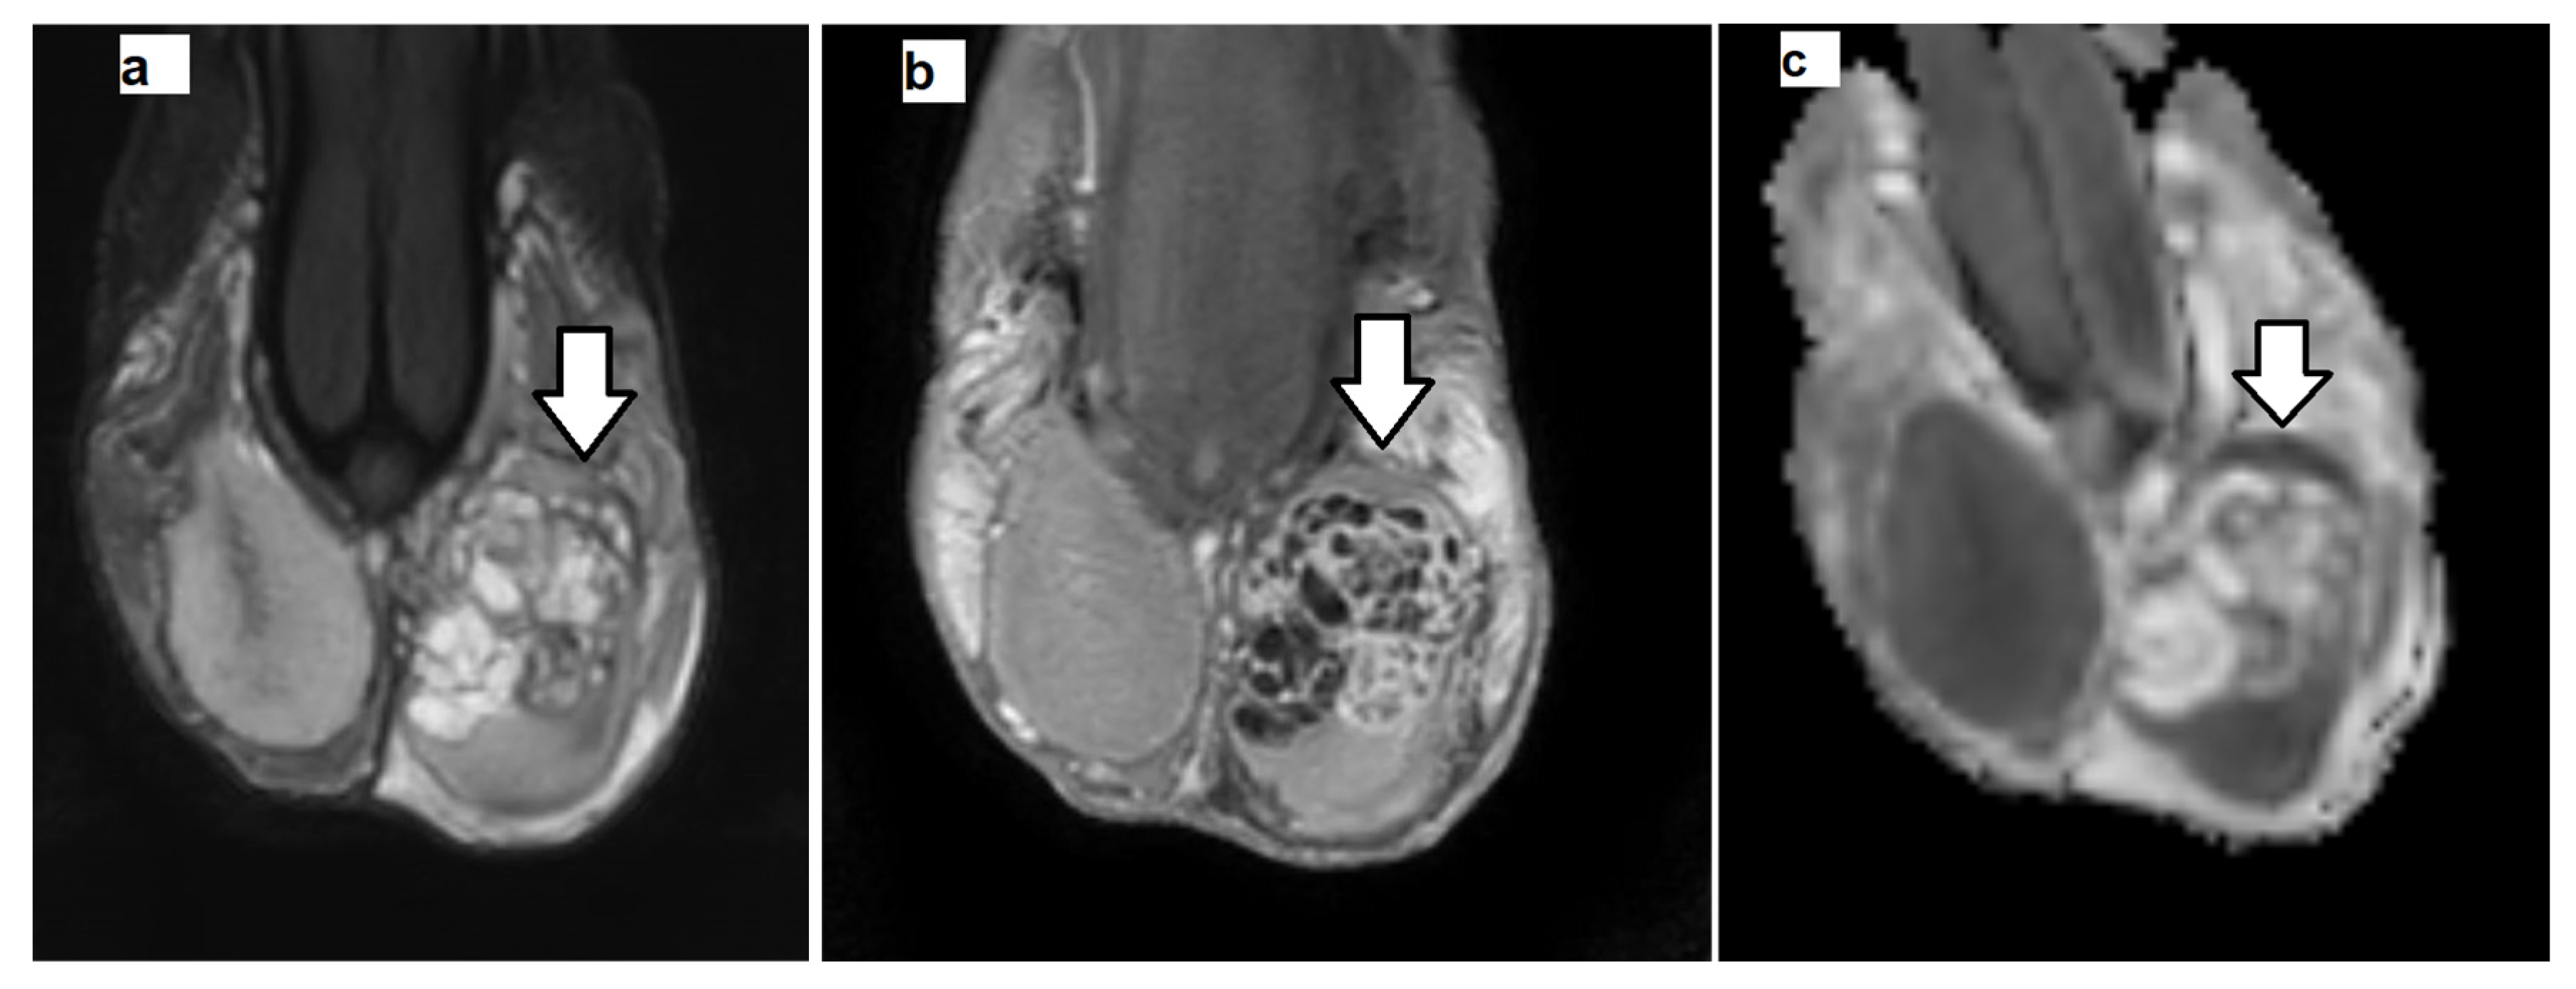

2.3. MRI Data Postprocessing